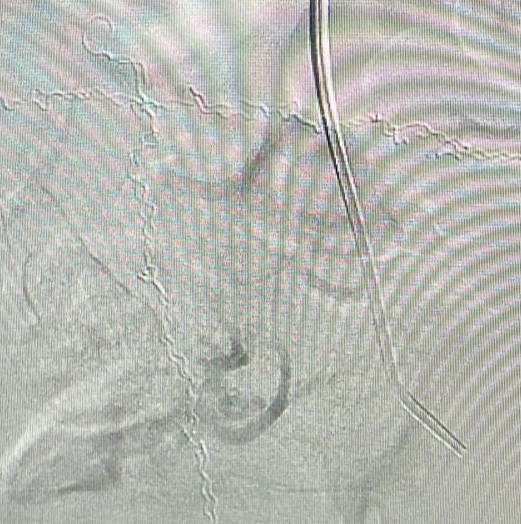

A equipe do Hospital Vaz Monteiro inovou novamente ao realizar, pela primeira vez na região, uma embolização de miomas uterinos, procedimento minimamente invasivo, com punção arterial e cateterização seletiva dos ramos uterinos tanto do lado direito quanto do lado esquerdo, visando administração de embosferas.

De acordo com Dr. Dirceu Dias Barbosa Sobrinho, coordenador da Divisão de Hemodinâmica do hospital, as embosferas são “estruturas desenvolvidas para interromper o fluxo arterial aos miomas, ocasionando sua regressão e desaparecimento, já que os tumores deixam de receber fluxo sanguíneo”.